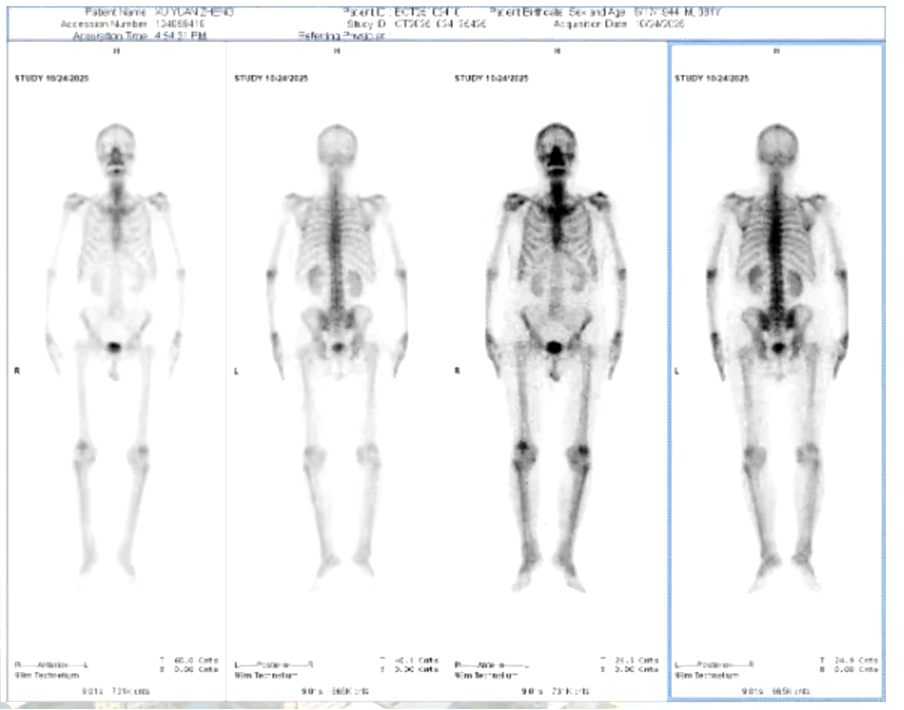

核磁共振

MR平扫(盆腔)+DWI(2025-10-23):前列腺癌术后改变。膀胱右后壁增厚并团片状异常信号影较前2021-12-23进展、新增,肿瘤复发/转移可能,建议结合增强扫描。双侧髂血管旁、腹股沟区小淋巴结显示。余较前大致相仿,建议复查。

MR动态增强(前列腺):前列腺癌术后改变。膀胱右后方占位,较前2025-10-23增大,结合病史,考虑肿瘤复发/转移可能性大。双侧髂血管旁、腹股沟区小淋巴结显示。